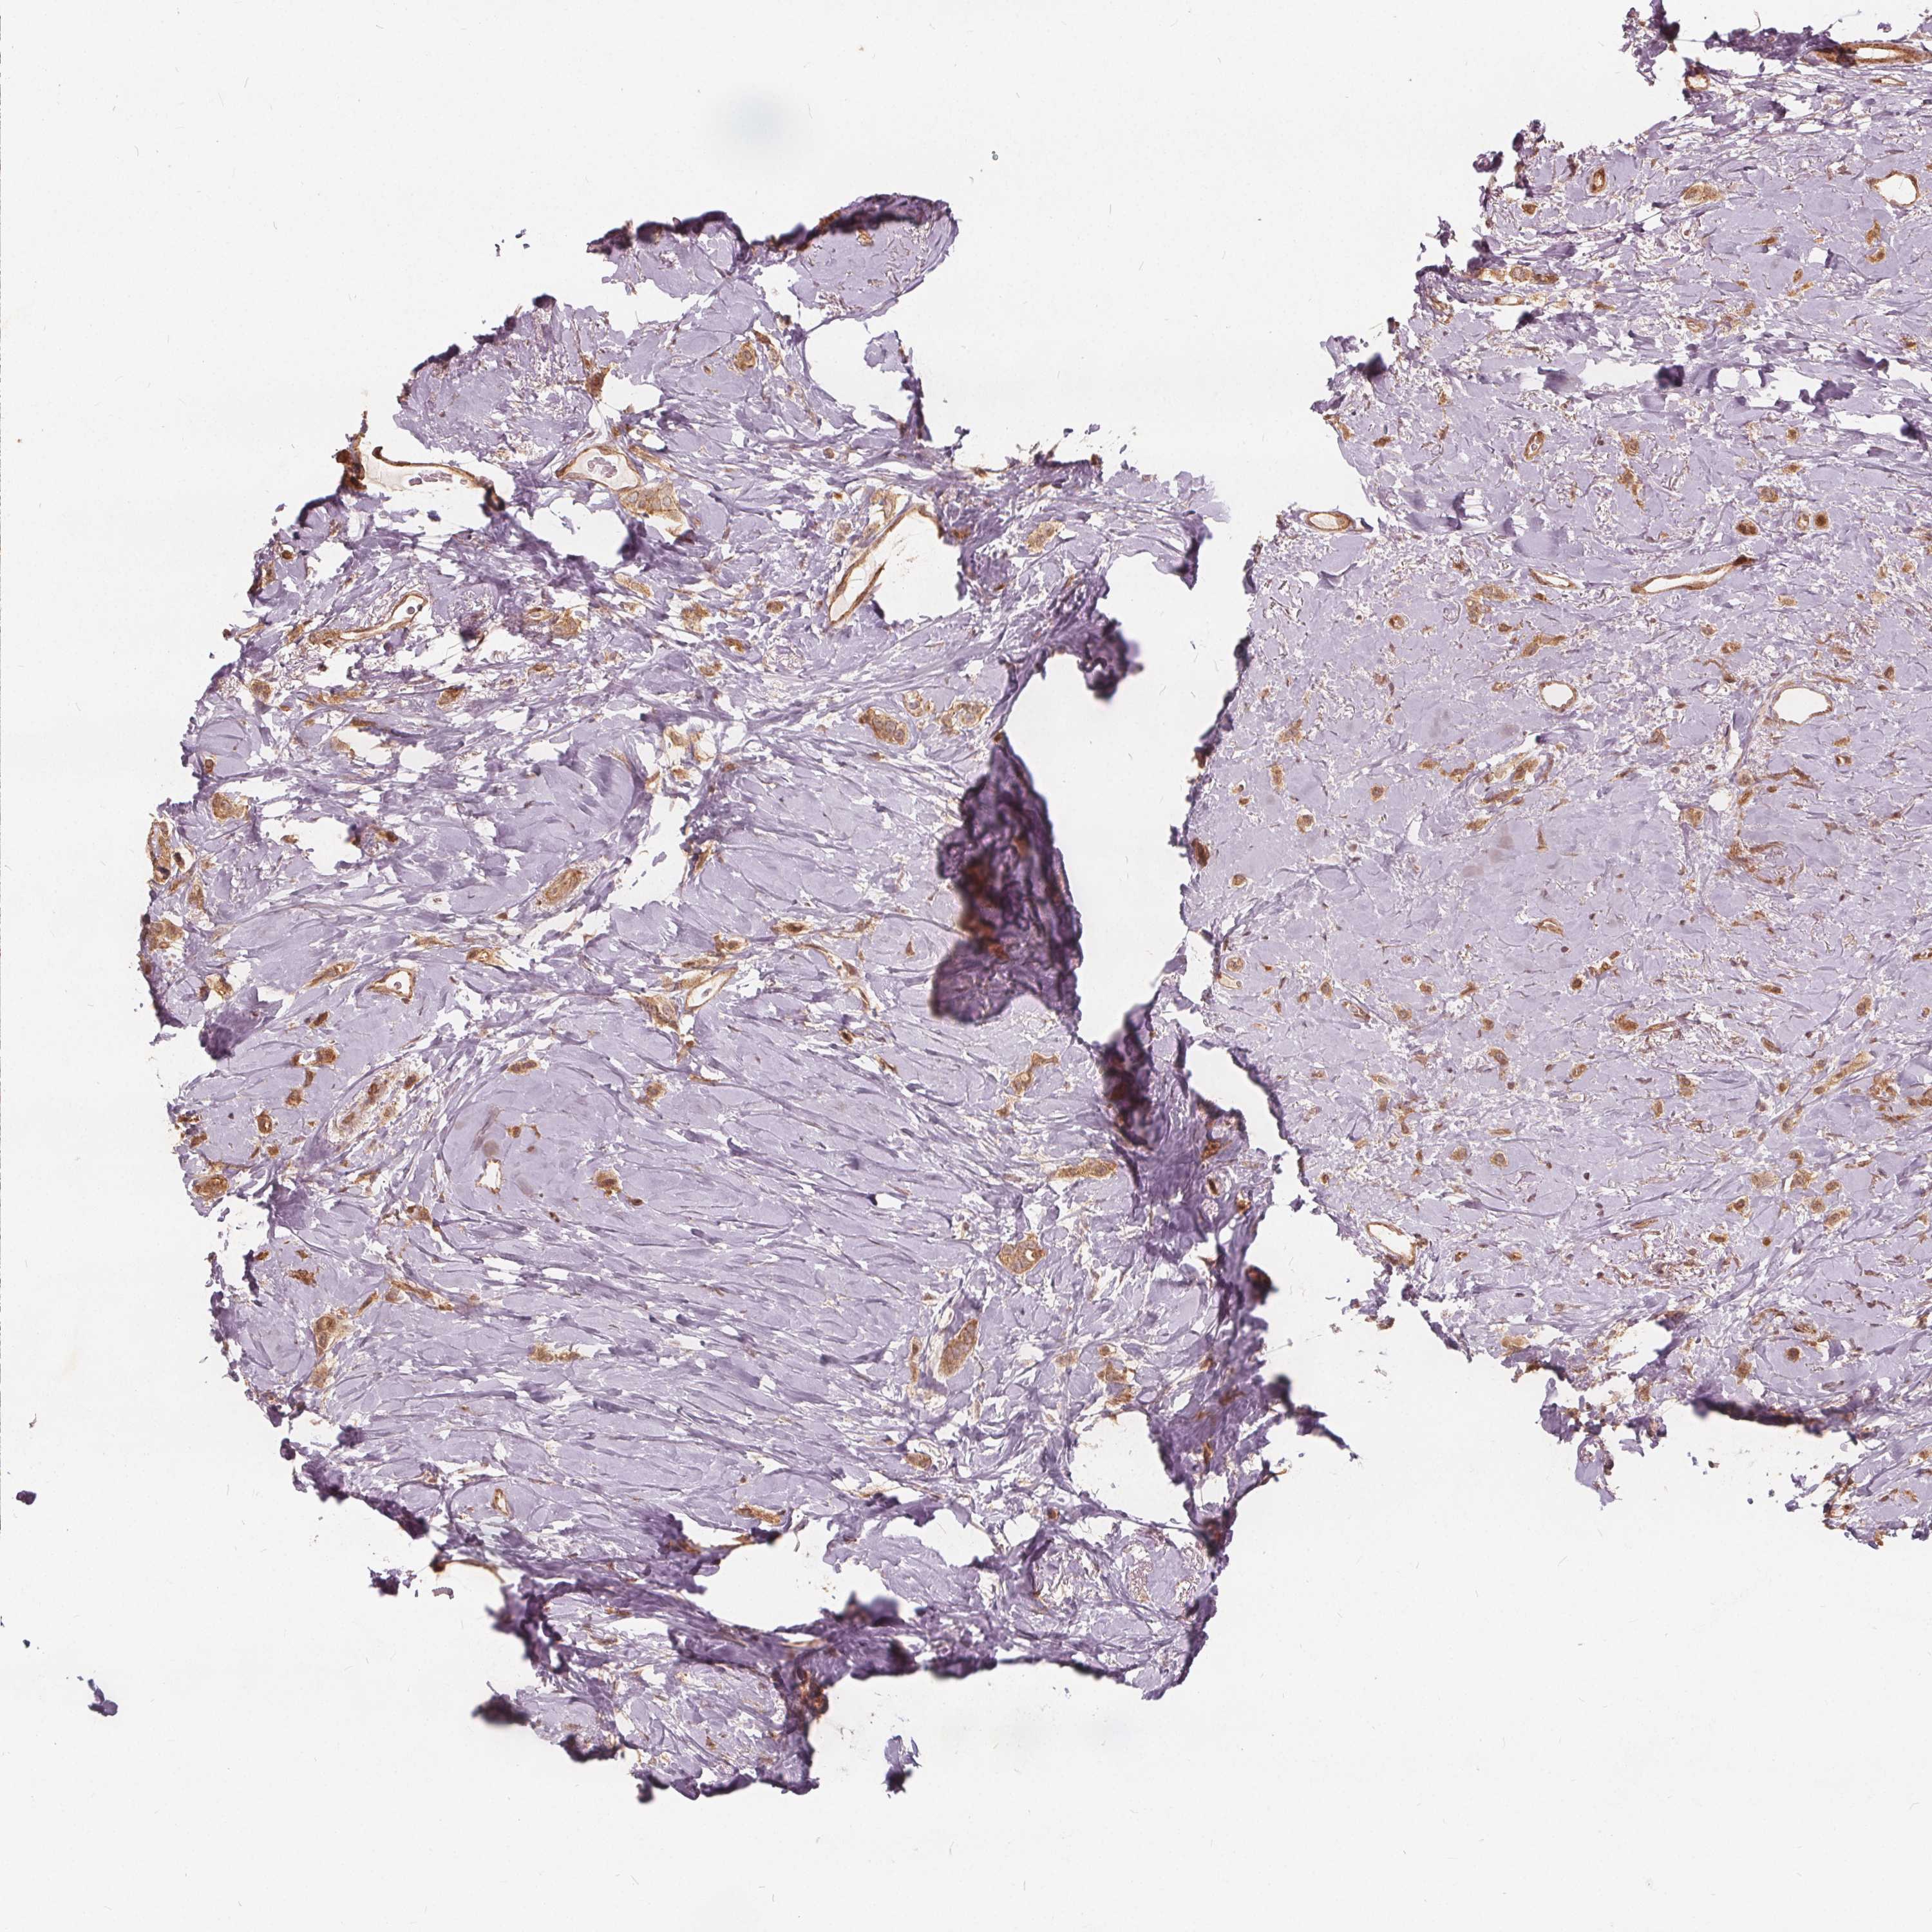

CANCER BREAST CANCER Show tissue menu

BRCA TCGA BRCA VALIDATION PROTEIN EXPRESSION

ANTIBODIES

AND

VALIDATION